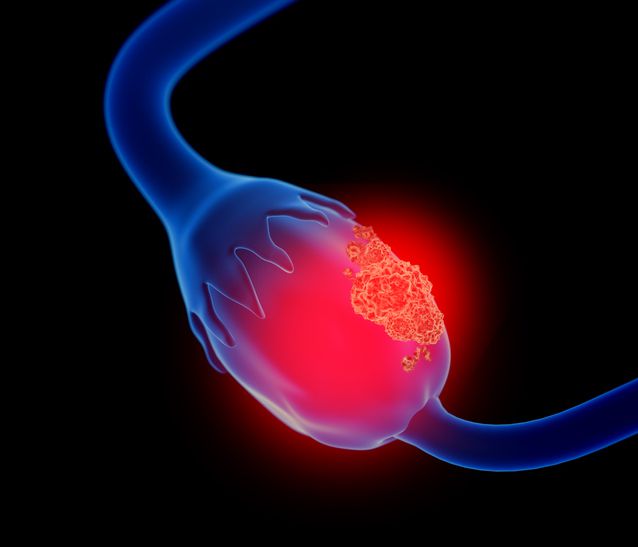

15. Ovarian cysts

Image Credit: Lars Neumann/iStock.